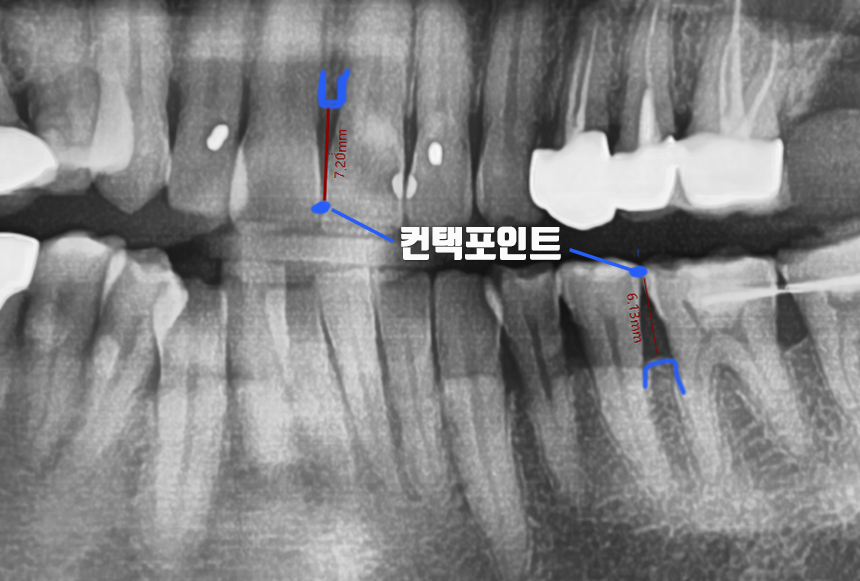

<사진> 직사각형 모양이 아닌, 뿌리쪽이 좁은 치아의 모습

치아 위쪽의 붙어있는 곳

즉, 치아와 치아가 만나는 곳을 컨택포인트(Contact Point)라고 합니다.

잇몸 쪽에는 3mm가량의 잇몸살과

그 아래로 잇몸뼈가 있는데

잇몸 뼈와 컨택포인트의 길이가 5mm가 넘어가게 되면,

블랙트라이앵글이 생깁니다.

잇몸뼈와 컨택포인트가 5mm이하로 정상적으로 치간유두가 차 올라 있는 경우

잇몸뼈와 컨택포인트가 5mm 이상으로 치간유두가 사라진 경우